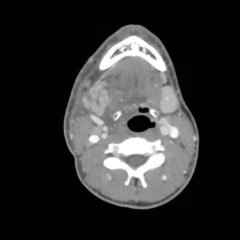

Cauliflower Ear Secondary to a Chronic Auricular Hematoma

A 40-year-old male with no past medical or surgical history presents to the emergency department for evaluation of a growth on his left ear over the past month. He reports a history of trauma three weeks ago, where he was involved in a bar fight and was punched in the ear. He denies any discharge, hearing loss, bleeding or being bitten. He states that since the injury his ear has become more swollen.

On exam, the patient has a gross deformity to the left pinna that was not painful to touch or fluctuant. Findings and history are consistent with cauliflower ear, secondary to a chronic auricular hematoma.